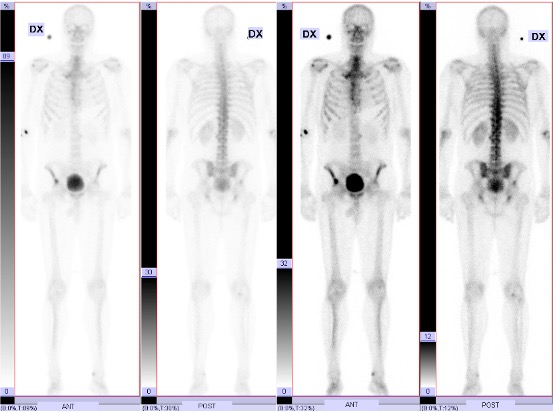

Efter utredning med scint och DT thorax/buk med i.v. kontrast konstaterades prostatacancer T4N1M1.

T4N1M1:

- T4: Lokalt mycket avancerad med urinblåsinvasion

- N1: Flera stycken stora (1-2,5cm) patologiska lymfkörtlar i bäckenet.

- M1: En 1 cm stor skelettmetastas i bäckenet.

Vid Diagnos

Vänster Njurbäckens tumör

Metastas i bäckenet